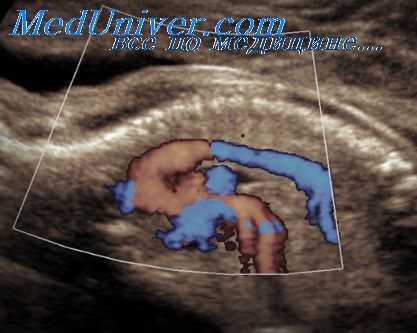

Визуализация венозного протока возможна при поперечном сечении верхней части живота плода на уровне его отхождения от пупочной вены. Затем включают режим ЦДК, и контрольный объем импульсно-волнового допплера устанавливается несколько выше области вхождения венозного протока (ближе к вене пуповины) - в точке, где при ЦДК регистрируется максимальная скорость кровотока. Его КСК характеризуются двухфазным характером при этом первый пик соответствует систоле желудочков (волна S), второй - диастоле желудочков (волна D), а самая низкая скорость кровотока отмечается при систоле предсердий (инцизура А).

Среди предложенных индексов для количественной характеристики КСК в венозном протоке, наиболее эффективно отражающим его гемодинамику, оказалось уголнезависимое отношение S/A между максимальными скоростями в систолу желудочков (S) и систолу предсердий (А).